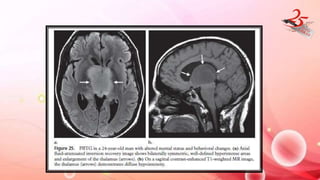

PRIMARY BILATERAL THALAMIC GLIOMA

• Thalamus is affected in 1-1.5% of brain tumors / contiguous spread

from pineal germ cell tumors.

• CLINICAL FEATURES : behavioral impairment ranging from

personality changes to dementia.

• IMAGING : T2 hyperintense and T1 isointense B/L symmetric mass

with no CE

• Low grade tumors characterized by absence of tumor progression

on serial MR images,